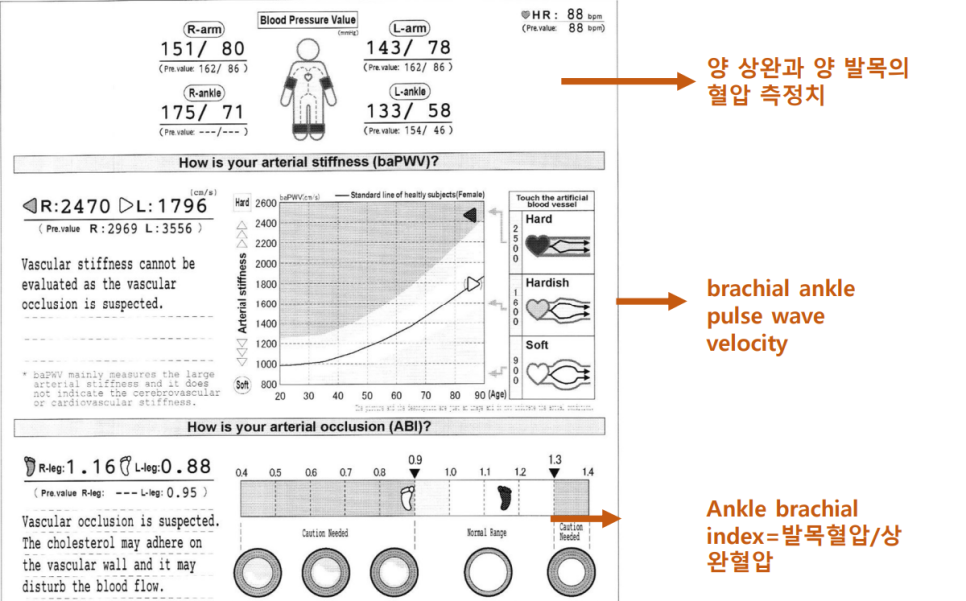

혈관 경직도 검사는 무엇입니까?팔과 다리의 혈압과 맥박의 파동을 분석하여 전신의 동맥은 얼마나 굳어 있는 것입니까? 혹시 막힌 데는 없나? 검사하겠습니다.

① ABI 점수(ankelbrachealin dex) : 손발의 혈압 차이가 얼마나 나는지 평가합니다. 팔 혈압은 높지만, 다리의 혈압은 너무 낮으면 다리의 혈관이 막힌 것이 아닐까요? 0.9보다 낮은 점수가 나오면 말초혈관질환이 의심됩니다.ABI 점수분석 1.0 1.0 1.0 정상 0.9-0.99 말초혈관질환? borderline/혈관내피세포의 이상발생 시사 0.7-0.89 말초혈관질환 있음 mild 0.5-0.69 말초혈관질환 있음 moderate < 0.5 심각한 말초혈관질환, 괴사발생가능성이 높은 점수가 낮을수록 혈관상태가 나쁠 수 있습니다.

② 혈류속도검사(baPWV(pulswave velocity) :> 1800cm/sec라면 동맥경직도가 높을 것으로 생각됩니다. 즉 혈관이 부드럽지 않고 딱딱하게 굳었다는 뜻이에요.